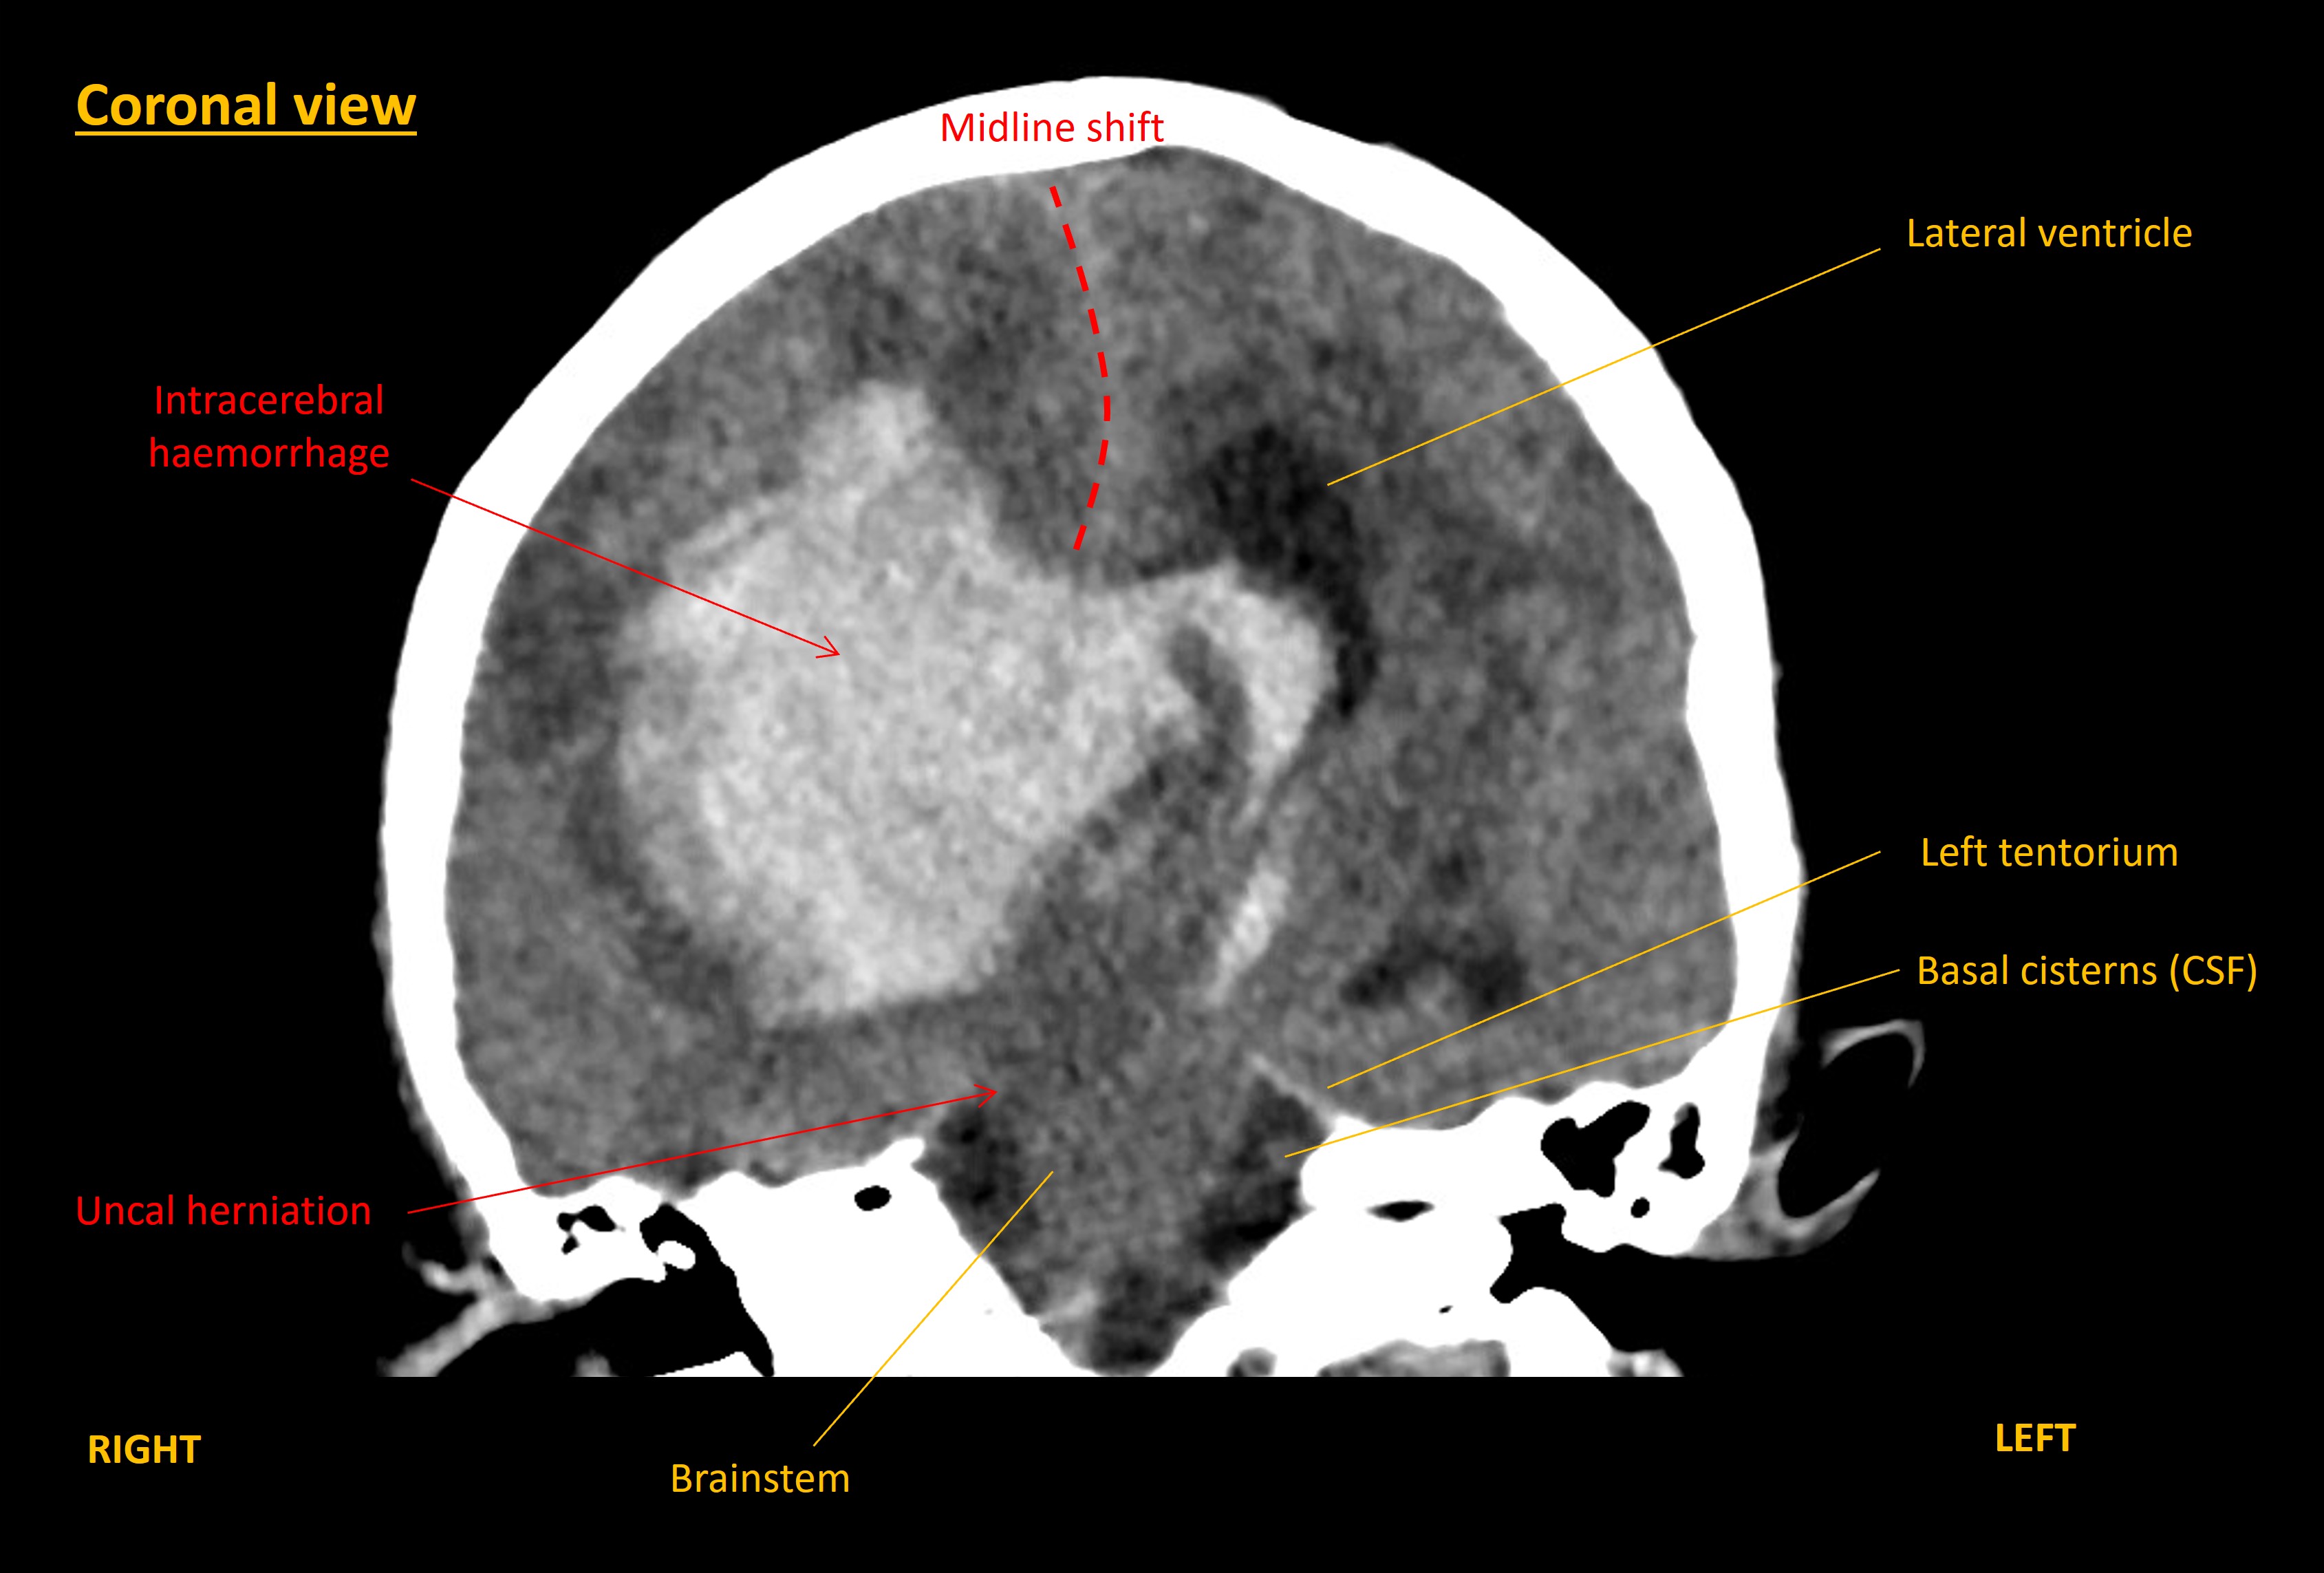

A CT brain was performed immediately. This showed a large right-sided intracerebral haemorrhage within the frontal and parietal lobes. The blood was causing mass effect with midline shift towards the left, and right uncal herniation. The haemorrhage had extended into the ventricles, including down to the fourth ventricle, with hydrocephalus.